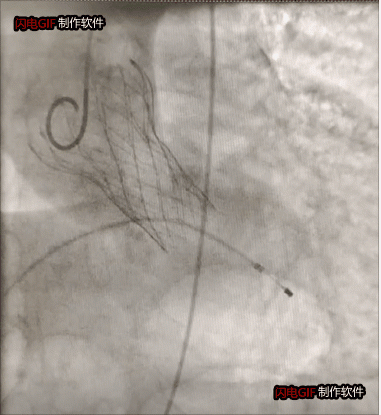

瓣狹窄患者瓣膜植入后影像

為避免激素可能對血管帶來的影響及血管入路并發(fā)癥,術(shù)前,徐州市一院心臟瓣膜病團(tuán)隊(duì)通過全面評估和檢測,為其設(shè)計(jì)了充分的應(yīng)對方案。術(shù)中,麻醉科副主任王德領(lǐng)、醫(yī)師趙盼盼克服了血壓極度波動(dòng),循環(huán)衰竭、崩潰等潛在風(fēng)險(xiǎn),為手術(shù)的順利開展鋪平道路。趙躍武在超聲科主任陳炳華、心胸外科副主任醫(yī)師嚴(yán)文俊、導(dǎo)管室護(hù)士長孫寧帶領(lǐng)的護(hù)理和技師團(tuán)隊(duì)的通力配合下,經(jīng)反復(fù)確認(rèn)入路血管彈性和脆性后,經(jīng)左側(cè)股動(dòng)脈切開,手術(shù)圓滿完成。